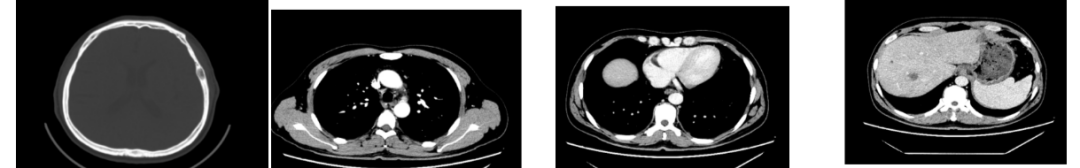

外院CT检查提示:1、两肺多发斑片状、结节影,性质待定,转移瘤?2、纵隔内多发肿大淋巴结;3、肝实质多发稍低密度影,性质待定(转移瘤可能性大)

2018-03-08 PET/CT示:胃癌(?)并全身多发淋巴结转移、肝脏多发转移、双肺上叶多发转移;

2018-11-14 CT(8周期化疗后):PD?

胃癌并肝转移化疗后,肝内转移灶大致同期;

慢性肝病,脾大、门脉高压(食管下段-胃底静脉曲张);

双肾小囊肿;

右肺中叶外侧段、左肺上叶下舌段及右肺下叶后基底段慢性炎症;

右肺上叶前段实性微小结节,炎性结节?建议定期复查;

纵隔淋巴结转移瘤,复查大致同前。